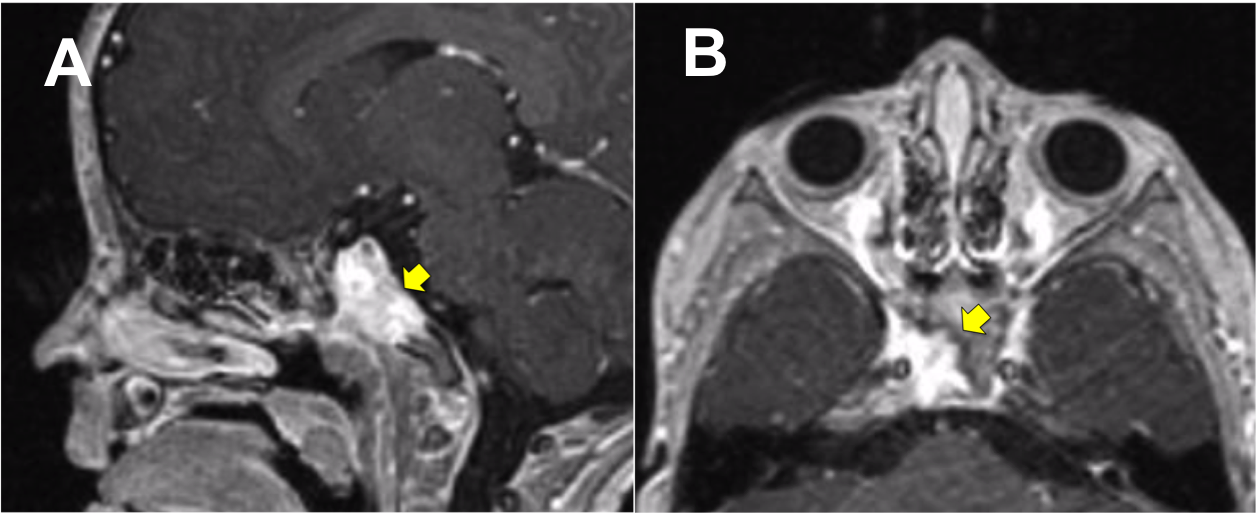

Resultados: Fueron intervenidos 8 pacientes entre los 2 y 14 años, con una edad promedio de nueve años y un seguimiento promedio de 16 meses. En el 75% se hizo una resección total del tumor. Un paciente requirió una reintervención y un paciente fue sometido a radiocirugía post-operatoria. 1 paciente falleció a pesar de múltiples intervenciones, quimioterapia y radioterapia.